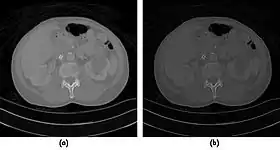

- A choice of filters can generally be selected to enhance either soft tissue features in the image or bone detail. Indeed, the image can be post-processed using a different filter after the scan has been completed if needed. Images can be generated to enhance bone detail or display subtle low contrast masses without the need to re-scan the patient. The filter choice therefore has a major impact on image quality. The two most common filters used in X-ray CT are those due to Ramachandran & Lakshminarayana (commonly called the Ram-Lak) and Shepp & Logan. Viewed in spatial frequency space, the former is essentially a ramp filter with a cut off frequency and the latter combines a smoothing filter with the ramp to attenuate high frequency noise. The ramp filter compensates for the artefacts introduced by the simple back projection process but does not compensate for the increasing noise content of the data with increasing frequency. Images of an axial tomogram reconstructed with a soft tissue and with a bone algorithm can be seen in Figure 7.14.

Fig. 7.15.2: Effect of window width and level on CT image display: (a) Level = 50; Width = 200. (b) Level = 50; Width = 400. The image in (a) is displayed with greater contrast and appears noisier than that in (b). |  Fig. 7.15.3: Effect of window width and level: (a) Level = -600; Width = 1700. (b) Level = -60; Width = 400. Image (a) displays the lung tissue more clearly, while image (b) can be used to highlight any pulmonary lesions. |

- Examples of image display manipulation are shown in the two figures above. In Figure 7.15.2, the same image of a slice through a patient's liver is displayed using a relatively narrow window (high contrast) and also with a wide window. The image with the narrower window appears noisier, but this is merely a reflection of the fact that the gray scale is spread over a narrow range of CT-numbers.

- Figure 7.15.3 illustrates the use of a relatively narrow window to highlight pathology in the lungs.